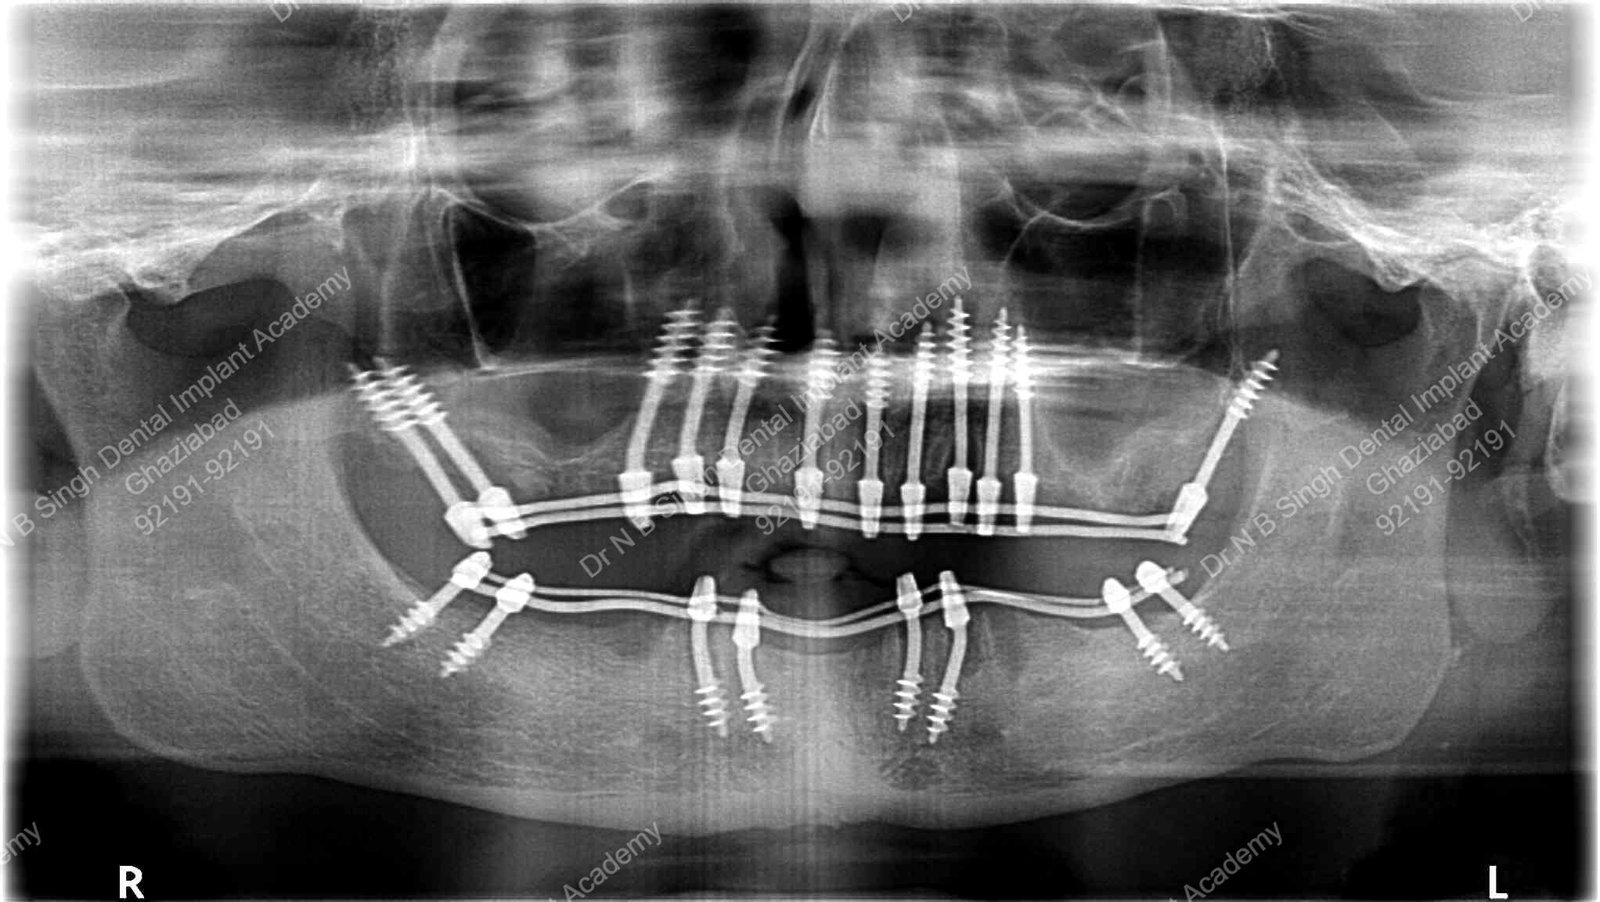

1006 Basal implant full mouth-DEEPAK